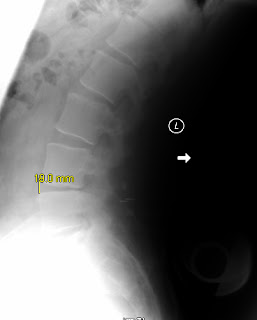

The X-Rays following my 6 month visit to the surgeon were finally sent to me and I've posted them underneath.

Here are the X-rays:-